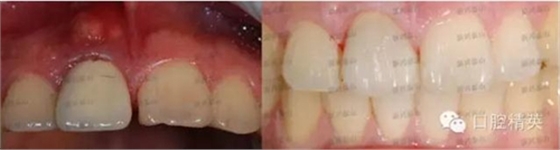

這是一個(gè)月前就診的患者,右上中切牙唇側(cè)牙齦有一個(gè)大膿包。在照片上可以看到烤瓷牙非常不美觀,一眼就能看出是假的,在前牙的位置,非常明顯,兩牙間還有很大的縫隙,顯得人比較呆板。

去掉烤瓷冠,去掉松動(dòng)老式螺紋固位釘,其內(nèi)大量的腐爛牙質(zhì),治療之后,剩余牙體很少,如上圖所見。根管治療后,牙齒健康,膿包消失,可以進(jìn)行后續(xù)的治療,讓患者拾回自信。

看看最后的成果吧。

怎么樣,真的是一次真實(shí)的蛻變吧!

牙齒在制作時(shí)花了點(diǎn)心思,既關(guān)閉了前牙縫隙,又沒有使這顆牙變得很大,患者非常滿意,很高興。

對(duì)比一下前后,視覺沖擊一下吧。

照片角度拍攝有些不一樣,但是變化還是非常明顯的。,右上中切牙唇側(cè)膿包還有點(diǎn)印跡,因個(gè)體的差異,慢慢會(huì)完全吸收,需要時(shí)間。

這是一顆鑄瓷牙,內(nèi)冠沒有金屬,消除了金屬對(duì)身體的刺激、對(duì)牙齦的刺激。金屬對(duì)牙齦刺激可能導(dǎo)致牙齦緣的變色即牙齦黑線,刺激牙齦退縮,對(duì)牙周易引起加重病變?,F(xiàn)在非金屬的牙冠越來越受到大家的認(rèn)可,全瓷冠擁有足夠的強(qiáng)度,既美觀又健康。鑄瓷不是最好的全瓷冠,依據(jù)患者的經(jīng)濟(jì)情況及牙齒情況,推薦鑄瓷牙,有很高的透光度,接近牙齒,美觀性很高,這是最好最適合患者的選擇。